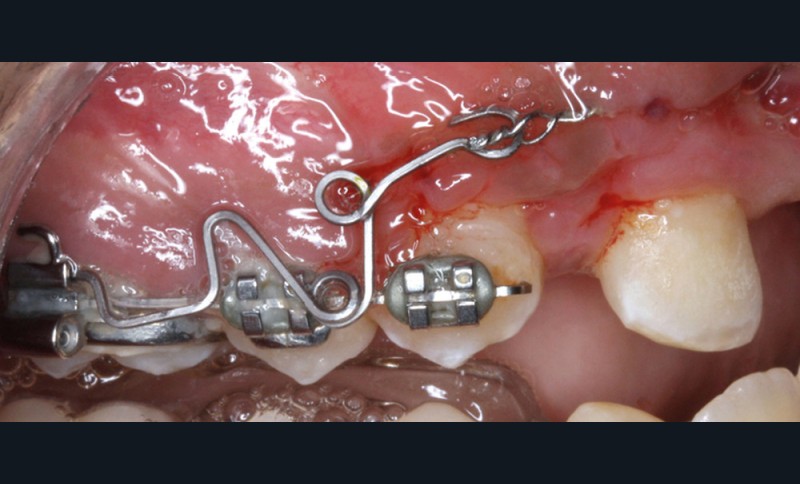

Dans un premier temps, l’extraction des 11 et 21 est réalisée. Un bouton est collé sur la 13, visible dans l’alvéole de la 11 afin de permettre sa désinclusion (fig. 2). La traction se fait à l’aide d’un arc TMA .016 x .022 en overlay afin d’avoir un axe de traction horizontal et vestibulaire évitant une résorption de la 12 à cette étape (fig. 3a,b) [3]. Ne pouvant pas mettre d’arc de Nance du fait de la position palatine des incisives latérales, il est convenu que des minivis d’ancrage peuvent être nécessaires si une perte d’ancrage postérieure est constatée (ce qui n’est pas le cas).